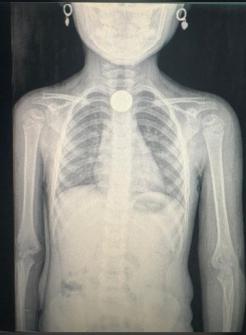

• Mesmo para objetos lisos (moedas), leve a criança ao médico para avaliação e exames (raio-X).

De acordo com a equipe médica, itens como moedas, pilhas de controle remoto e pequenas peças de brinquedos são frequentemente ingeridos de forma acidental. Ao dar entrada na unidade, a criança passa por avaliação na emergência e exames de imagem para identificar a localização do objeto no aparelho digestivo.

Um dos casos recentes ocorreu na sexta-feira (27), quando uma criança ingeriu uma moeda. O objeto foi retirado no dia seguinte atraves de uma endoscopia, paciente ja teve alta. O Hospital Regional informou o departamento de jornalismo da Liberdade FM que a criança segue sem complicações.